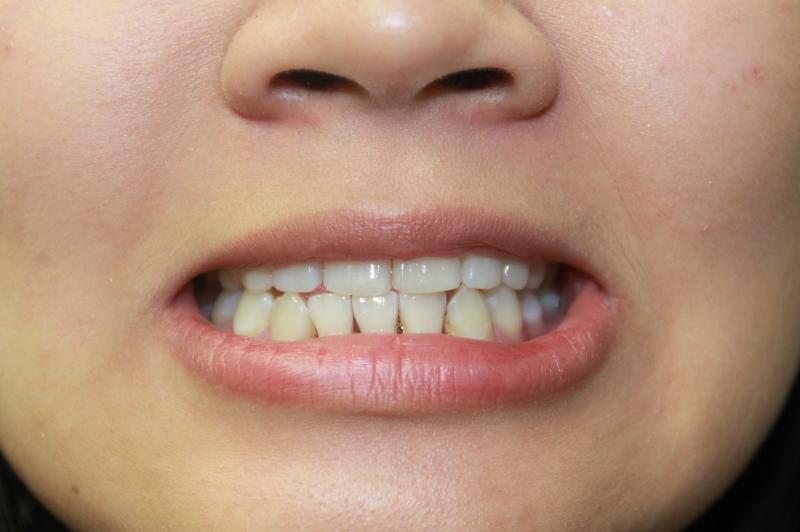

INVISALIGN - 13 months, 1 lower tooth removal, 1 series of aligners to align teeth and create the proper amount of space for 2 cantilever bridge to replace congenitally missing cuspids. COSMETIC DENTISTRY - 2 porcelain cantilever bridges and cosmetic bonding to reshape incisors and close gingival spaces. TOTAL TREATMENT TIME, 15 months

Cosmetic Dentistry, Mid-line Asymetry, Missing Teeth, Severe Crowding